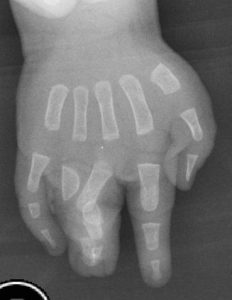

A união pode abranger apenas a pele e gordura (ver Fig. 1), ou pelo contrário, incluir unha (ver Fig. 2), falanges, tendões e outros tecidos- neste caso é denominada complexa (ver Fig. 3). Pode ainda conter falanges acessórias, denominando-se então como complicada.

Fig. 3: união de varias falanges, algumas delas, anormais